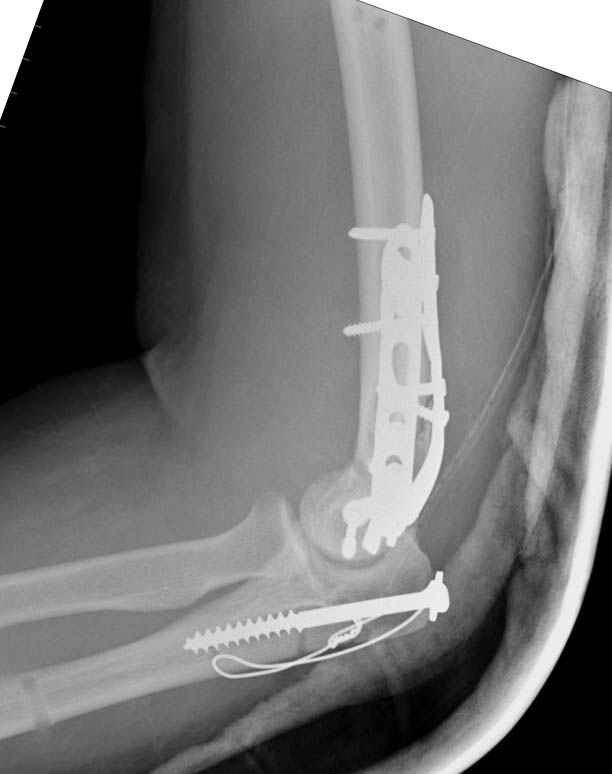

На шестой день сделали открытую репозицию чрезлоктевым доступом двумя locking plate, локтевой нерв был ушибленным, после операции положительная динамика в Flexor Carpi Ulnaris. Фиксацию локтевого отростка произвели tension band technique с дополнительным шурупом.

Этапы операции на снимках....